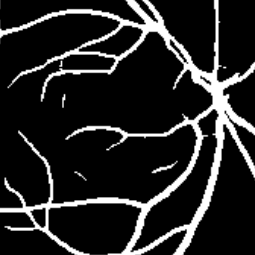

Semantic segmentation of blood vessels is an important task in medical image analysis, but its progress is often hindered by the scarcity of large annotated datasets and the poor generalization of models across different imaging modalities. A key aspect is the tendency of Convolutional Neural Networks (CNNs) to learn texture-based features, which limits their performance when applied to new domains with different visual characteristics. We hypothesize that leveraging geometric priors of vessel shapes, such as their tubular and branching nature, can lead to more robust and data-efficient models. To investigate this, we introduce VessShape, a methodology for generating large-scale 2D synthetic datasets designed to instill a shape bias in segmentation models. VessShape images contain procedurally generated tubular geometries combined with a wide variety of foreground and background textures, encouraging models to learn shape cues rather than textures. We demonstrate that a model pre-trained on VessShape images achieves strong few-shot segmentation performance on two real-world datasets from different domains, requiring only four to ten samples for fine-tuning. Furthermore, the model exhibits notable zero-shot capabilities, effectively segmenting vessels in unseen domains without any target-specific training. Our results indicate that pre-training with a strong shape bias can be an effective strategy to overcome data scarcity and improve model generalization in blood vessel segmentation.